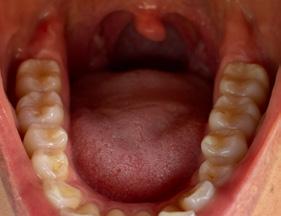

Estudios de inicio intraorales

Fotografías en la lateral derecha tenemos: relación molar clase I bilateral y relación canina clase I bilateral, líneas medias dentales coincidentes (Figura 3), -5 mm de overjet, 10% de underbite, las arcadas superior e inferior son ovaladas, apiñamiento severo superior e inferior (Figura 4).

Figura 3. Intraorales frente, lateral derecha e izquierda. Figura 4. Intraoral oclusal superior e inferior.